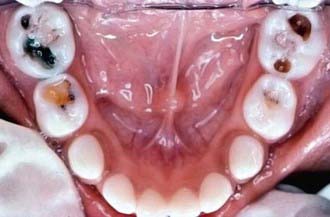

The development of dental caries depends on interrelationships among the tooth surface, dietary carbohydrates, and specific oral bacteria. Organic acids produced by bacterial fermentation of dietary carbohydrates reduce the pH of dental plaque adjacent to the tooth to a point where demineralization occurs. The initial demineralization appears as an opaque white spot lesion on the enamel, and with progressive loss of tooth mineral, cavitation of the tooth occurs (Fig. 304-1).

Figure 304-1 Initial carious lesions (white spot lesions) around the necks of the maxillary central incisors.